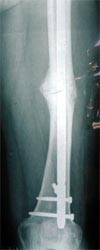

病例二、患者62岁,股骨中1/3骨折骨不连2年,3次钢板手术失败,明显畸形。

同上述方法治疗,9个月后骨折愈合。